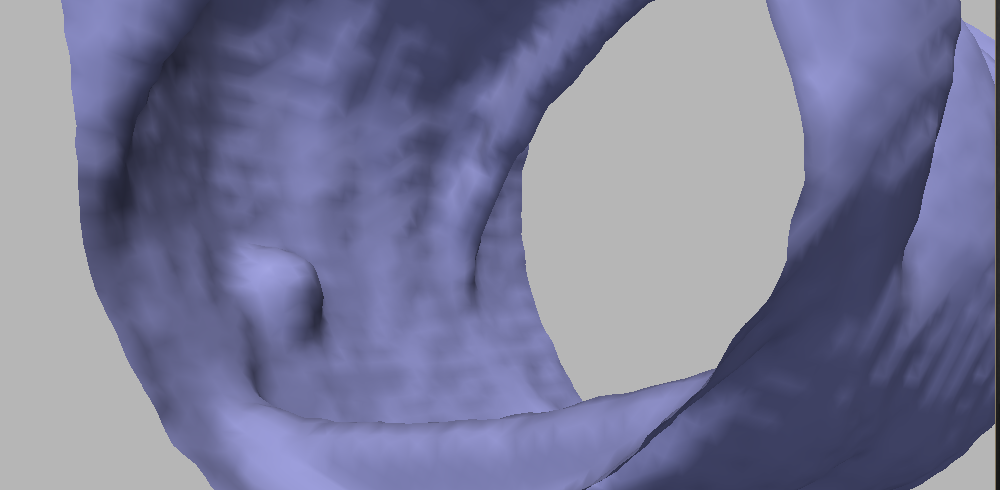

Figure 7 shows the result after a few iterations; comparing to Figure 5, it can be readily seen that this motion achieves a better trade-off in terms of noise reduction and polyp preservation. Figure 8 evidences the difference with a comparative image: the result of the motions by and are shown in gray and in orange, respectively. On the polyp protrusion, the orange surface is above the gray surface, while the opposite is observed in the surrounding area. This shows that the evolution by leads to better polyp enhancement.